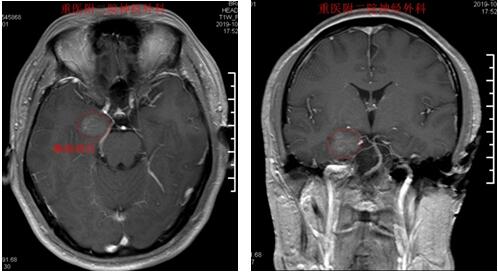

男性,32岁,因“反复癫痫发作5年”入院

术前MRI检查提示癫痫病灶位于右侧海马

术后1年随访,无癫痫发作